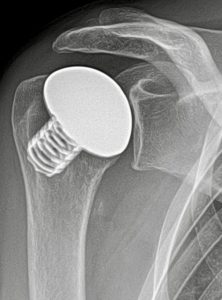

Dr. Rummel als ausgewiesener Fachmann für den Bereich der Endoprothetik erklärt „Eine fortgeschrittene Schulterarthrose, irreparable Sehnendefekte, schweres Rheuma oder ein Absterben des Oberarmkopfes können das Gelenk aber so stark schädigen, dass kein Weg an einer Prothese vorbeiführt.“ Erfreuliche Nachrichten bzgl. der Haltbarkeit hat Dr. Rummel für diese Patienten: "Nach zehn Jahren sind noch über 95% fest implantiert."

(Bild unten: Kurzschaftprothese Schulter (Typ Eclipse, Fa. Arthrex))